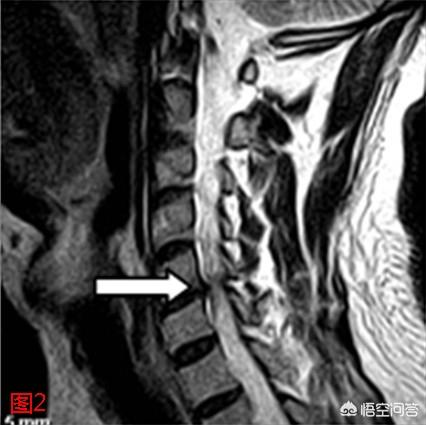

5.頚椎椎間板ヘルニア

質問で話したように、下部頚椎の椎間板ヘルニアは神経を圧迫して手のしびれを引き起こすことがありますが、首の違和感を伴うことが多く、画像診断でヘルニアがあると診断されるべきではありません。

頚椎椎間板ヘルニアは、一般的にフィルムによって診断されますが、私はあなたに診断技術を教えることは、首の実験を押すことです、あなたは椅子にまっすぐ座って、頭の上に別の人の手を聞かせて、ゆっくりと圧力を加え、手のしびれが症状を悪化させる場合は、頚椎椎間板ヘルニアと診断することができます!頚椎椎間板ヘルニアの急性期は主に静養し、回復期の3、4日後に推拿調整と灸血調整、補助牽引を行うことができます!

ただ文字通りに理解すれば、神経を圧迫しているのは頸椎であって、椎間板が神経を圧迫しているのでも、脊髄の神経を圧迫しているのでもない。原因がはっきりしてこそ、頚椎症の種類をより正確に特定でき、その上で治療法を選択できるからです。

頚椎症には大きく分けて7つのタイプがあり、あなたがおっしゃるのは脊髄頚椎症ではなく神経根頚椎症でしょう。

神経根性頚椎症は、髄核のヘルニアや脱出、後方小顔関節の骨棘や外傷性関節炎、鈎関節の骨棘形成、隣接する3つの関節(椎間関節、鈎関節、後方小顔関節)のゆるみや変位などによって引き起こされ、これらすべてが脊髄神経根の刺激や圧迫を引き起こし、その結果、頭、首、肩、さらには腕の指の筋肉痛やしびれを引き起こします。

神経因性頚椎症は手のしびれの主な原因であり、頚椎椎間板変性とその二次的変化によって神経根が圧迫され、主に上肢のしびれとして現れる疾患である。

手のしびれは、頸椎の関節や靭帯の増殖、椎間板ヘルニアなどにより、対応する神経根が圧迫されることで起こる。